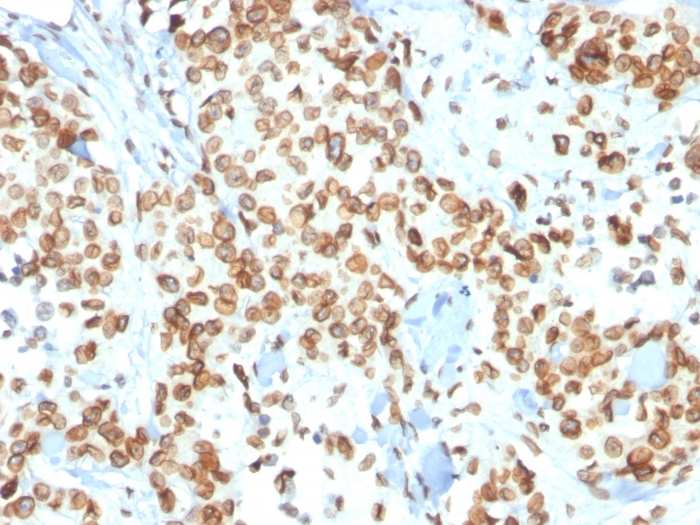

Formalin-fixed, paraffin-embedded human Renal Cell Carcinoma stained with Emerin Mouse Monoclonal Antibody (EMD/2167).